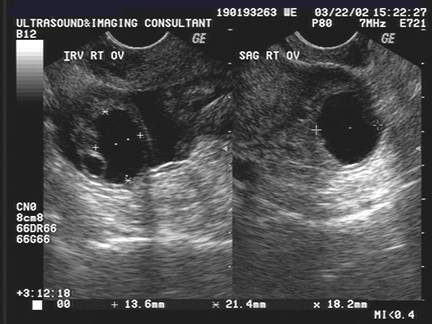

OVULATION

Baerwald et al (4) characterized changes in luteal form and function using serial transvaginal ultrasonography, gray-scale imaging and analysis of serum hormonal patterns. The hypothesis that changes in luteal morphology and endocrine secretion would be detected during the interval between two subsequent ovulations seems to be supported.

Two morphological types of CL were observed following ovulation:

·         with a central fluid-filled cavity (CFFC) (78%),

·         without a central fluid-filled cavity (CFFC).

The incidence of corpora lutea containing a CFFC was greatest immediately following ovulation and then subsequently declined. Prior to this study, the physiological significance of the cystic cavities has not been well-documented. CFFCs were attributed to the chance occurrence of follicle rupture across a vascular component of the follicle resulting in leakage of blood into the follicular lumen. Measurements of the luteal area, defined as the area between the external border of the CL and the internal border of the CFFC, and luteal numerical pixel value (NPV) were the main outcome measures of the study. Luteal area seems highly correlated with progesterone concentrations during the interovulatory interval (IOI). Luteal area and estradiol concentrations, however, were not as strongly correlated. The regressing CL was present in the follicular phase but it did not appear to be functional as indicated by basal levels of serum progesterone and estradiol. This study investigated also the quantitative changes in luteal echotexture that seems reflective of changes in the morphological and physiological status of the CL in women. A decrease in luteal NPV occurred during luteal development in association with an increase in luteal area, progesterone and estradiol concentrations, while the subsequent increase in NPV during luteal regression occurred in association with a decrease in luteal area, progesterone and estradiol concentrations (4). Decreased NPV during luteinization was attributed to increased vascularization of luteal tissue and a corresponding decreased tissue density (4). Increased NPV during luteolysis was attributed to decreased vascularization and replacement of luteal tissue with fibrous connective tissue, reflective of increased tissue density. Unfortunately, in the present study, it was not possible to prove this theory because color Doppler evaluation was not reported (4).